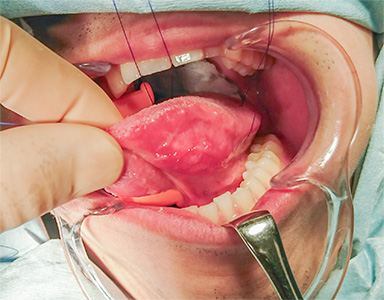

早期舌がんの治療(手術)の流れ

舌左側縁に癌を認める